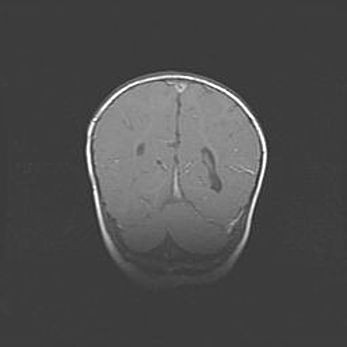

Множественные кисты обоих полушарий головного мозга, наибольшая из них в правой затылочной области. Ассиметричная атрофическая гидроцефалия.

Возраст: 7 месяцев

Вес: 5660 г

Пол: мужской

Окружность головы: 41,5 см

Срок гестации: 28-29 недель

Кисты головного мозга развиваются в результате многоочаговых некрозов вещества мозга и возникают вследствие перенесенной перинатальной инфекции, менингитов, энцефалитов, асфиксии, родовой травмы, расстройств мозгового кровообращения различного генеза. Образованию кист в веществе головного мозга плодов и новорожденных способствуют такие факторы, как высокое содержание в нем воды, недостаточная (или отсутствие) миелинизация и слабая астроглиальная реакция на повреждение.

Кисты могут сочетаться с гидроцефалией и другими поражениями головного мозга.